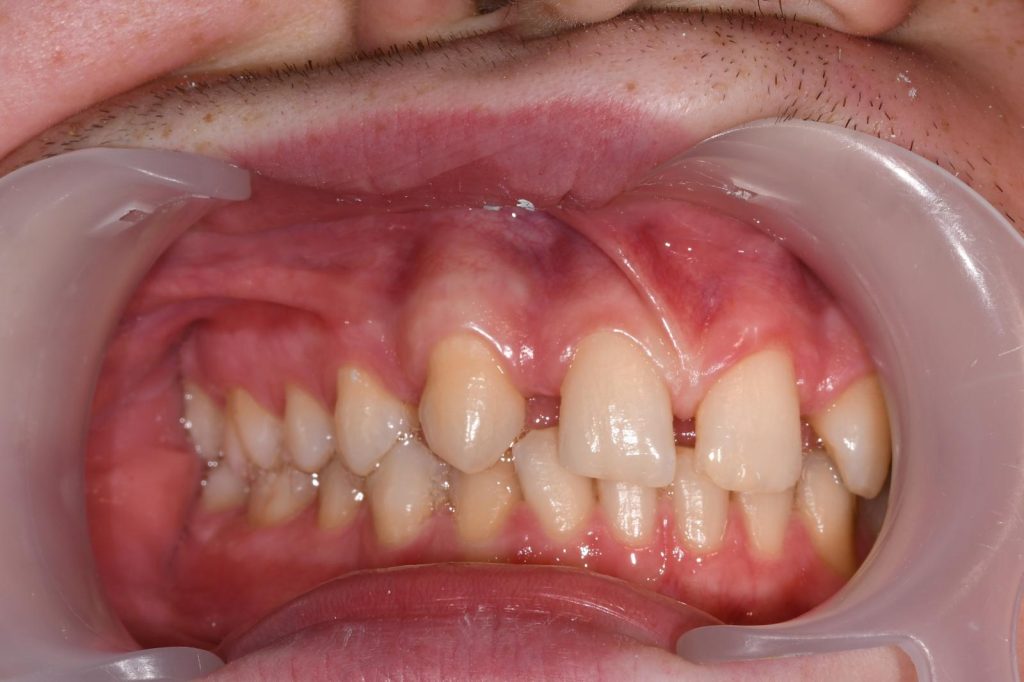

Kako bi se omogućilo postavljanje implantata na pravilan način, prvo je bilo potrebno ortodontskom terapijom napraviti dovoljno prostora za buduće dvojke. Ortodont je pažljivo rasporedio zube tako da se stvori simetričan i prirodan izgled osmijeha.

Ortodontska terapija - Hipodoncija

Nakon ortodontske terapije

Nakon završetka ortodontske terapije, pomoću dijagnostičkih metoda utvrđeno je da pacijent ima dovoljno kosti za ugradnju implantata. Ugradnja dentalnih implantata izvedena je precizno, vodeći računa o optimalnom položaju implantata za kasniji estetski rezultat.